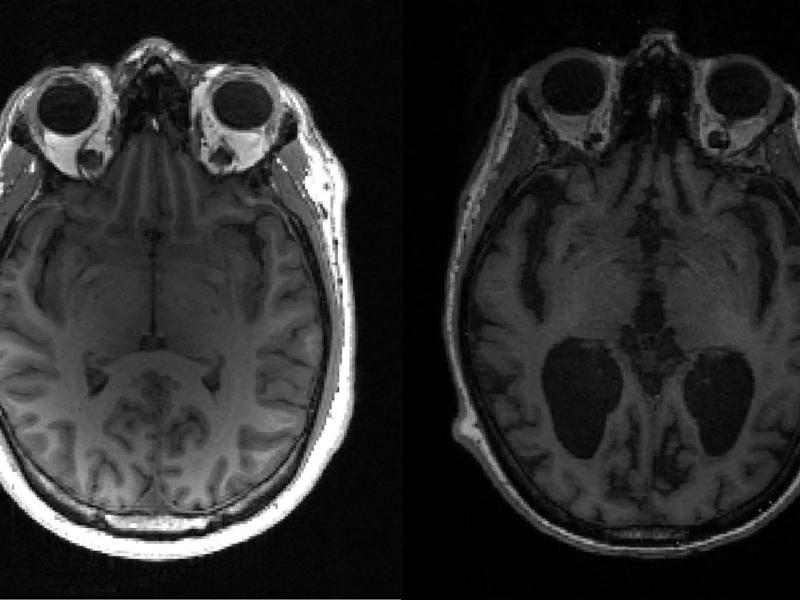

بهداشت و درمان محقق ایرانی: مکملهای کلسیم خطر ابتلا به زوال عقل را افزایش نمیدهند نگار قاسمیفرد، نویسنده اصلی پژوهش، میگوید این یافتهها به بیماران و پزشکان اطمینان میدهد که مصرف مکمل کلسیم از نظر ابتلا به زوال عقل، برای زنان مسن بیخطر است خطر مصرف سرخود مکملها؛ کارشناسان در مورد منیزیم، کلسیم و آهن هشدار میدهند وگانها ۴۳ درصد بیشتر در معرض شکستگی استخوان هستند محققان میگویند کلسیم کلید درمان سرطان است